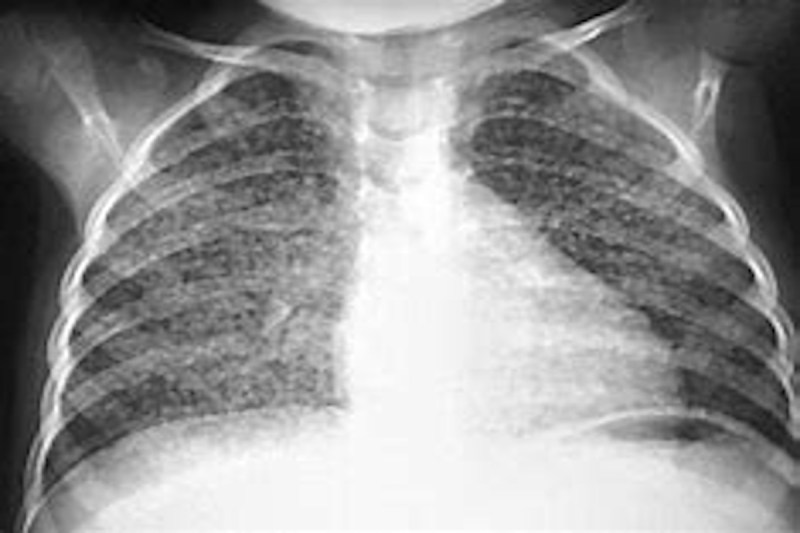

फेफड़े और आंत की टीबी तो पकड़ में आ जाती है लेकिन शरीर के अन्य हिस्सों में हुए संक्रमण का पता बहुत देर से चलता है। तो वहीं दिमाग, हड्डी, स्पाइन, जेनाइटल अंगों के साथ आंखों की टीबी (इंट्राऑक्युलर टीबी) तेजी से बढ़ रही है। आंख की टीबी की पहचान न हो पाना डॉक्टरों के लिए चुनौती बना हुआ है। ये जानकारी स्टेट टीबी अफसर डॉ. शैलेंद्र भटनागर ने कही।

टीबी की साल 2022 की रिपोर्ट के मुताबिक उत्तर प्रदेश में एक्सट्रा पल्मोनरी टीबी के केस फेफड़ों की टीबी के केस की तुलना में एक तिहाई हैं। रिपोर्ट बताती है कि फेफड़े की टीबी के यूपी में बीते साल कुल 3,41,444 आए जबकि इसी दौरान एक्सट्रा पल्मोनरी टीबी के 1,12,268 केस प्रदेश में पाए गए हैं।